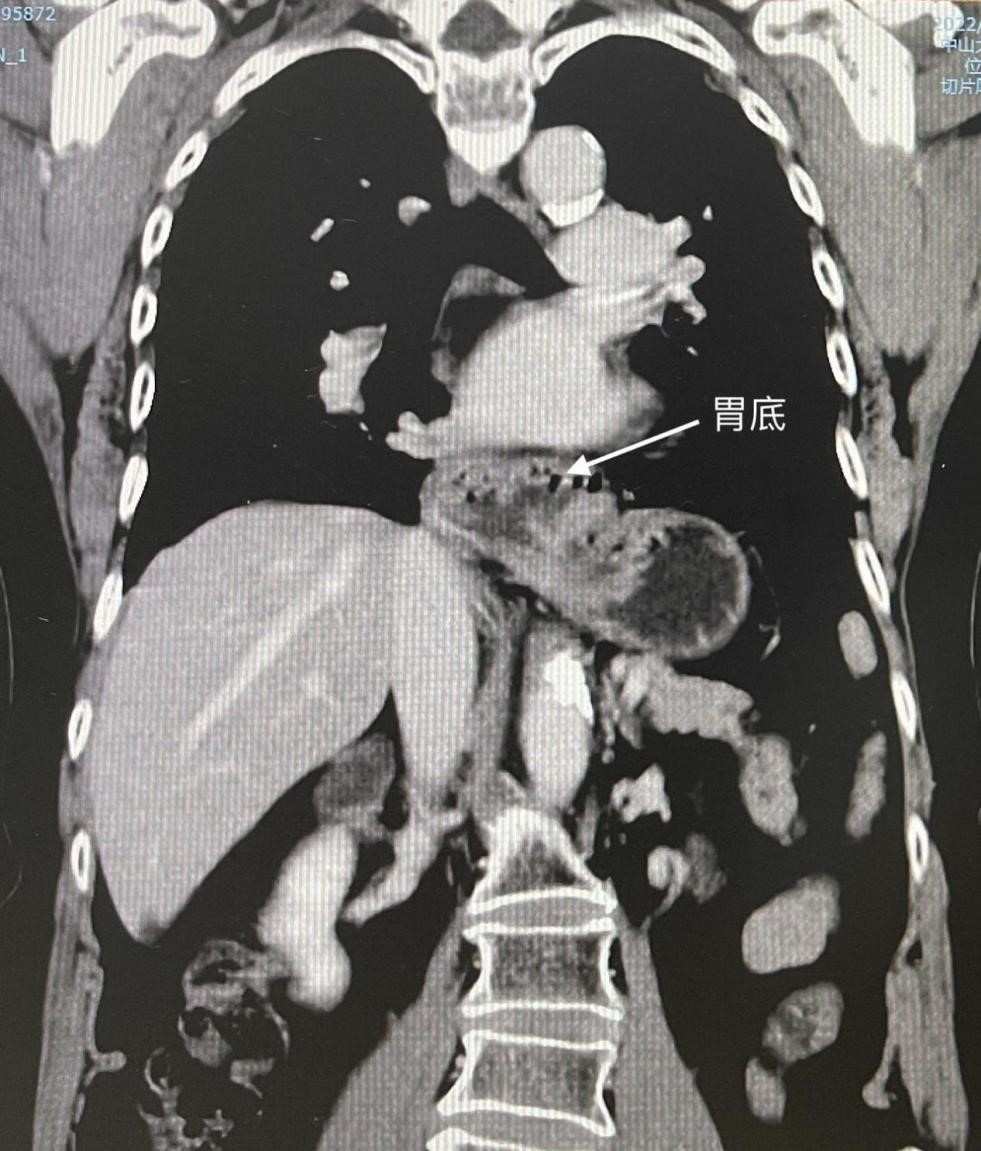

不用放置胃管,也不需要放置引流管,肚皮上仅有4个小孔,施行腹腔镜下食管裂孔疝修补+胃底折叠术后,王阿姨轻松摆脱久治不愈的咳嗽,术后第二天便顺利出院。

据了解,人体胸腔与腹腔之间有一块重要的肌肉——膈肌。食管穿过膈肌的裂孔处与胃相连,此裂孔即食管裂孔。正常情况下,食管裂孔刚好容纳食管通过。但如果腹腔内压力增大或食管裂孔周围结构过于松弛,腹腔内的脏器就可以通过食管裂孔进入胸腔,从而形成食管裂孔疝。